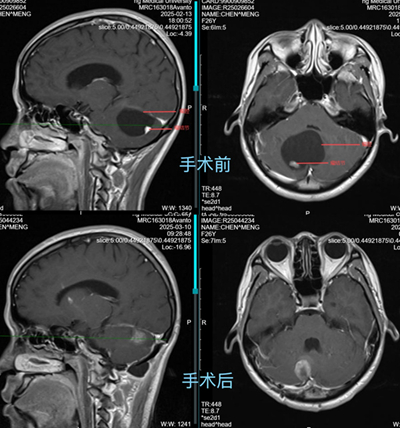

在消化內科,小林經胃腸鏡、腹部CT等系統檢查后,被告知未發現消化道病變。那么,到底是什么原因引起小林持續惡心、嘔吐伴步態不穩呢?此時,重醫附屬大學城醫院消化內科團隊捕捉到小林伴隨的共濟失調體征?!皣I吐伴步態不穩要警惕神經系統病變?!毕瘍瓤漆t生說道,隨后,立即啟動多學科會診。經顱腦磁共振成像(MRI)檢查,結果顯示:小林小腦半球存在巨大的囊實性占位性病變,是小腦巨大腫瘤。輾轉2月,小林的病因終于浮出水面。

手術前后MRI對比。重醫附屬大學城醫院供圖

回憶起一個多月前,小林被轉到神經外科的樣子,重醫附屬大學城醫院神經外科副主任唐榮銳不免心里咯噔一下?!爱敃r情況非常緊急,她的小腦占位性病變已經壓迫第四腦室和腦干,若不及時手術,可能導致腦干功能障礙、急性梗阻性腦積水等嚴重并發癥,甚至危及生命?!苯涍^急診手術,小林的腦內腫瘤被順利切除,徹底解除壓迫,惡心、嘔吐癥狀也很快消失。